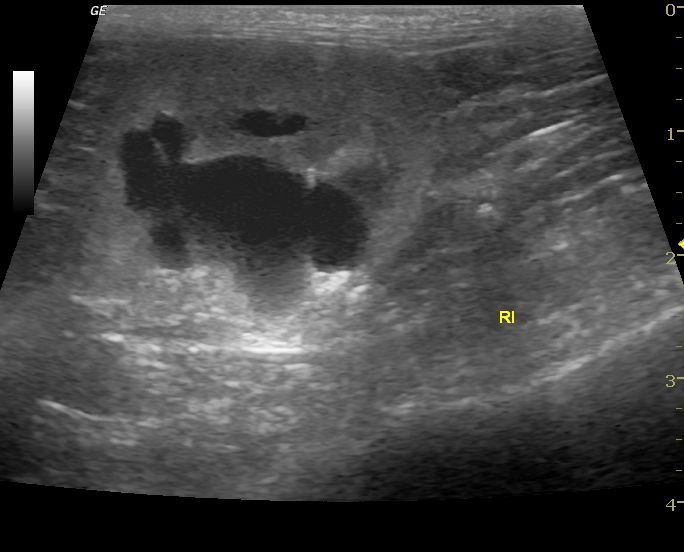

La Ecografía permite una exploración completa de los distintos órganos aportando datos objetivos para conseguir un diagnóstico preciso , establecer un tratamiento adecuado y realizar un seguimiento de cada caso.

La ecografía como diagnótico de gestación es a día de hoy el método más fiable durante el primer trimestre, además nos aporta datos para predecir la fecha de parto, y realizar un seguimiento del desarrollo de los fetos, pudiendo evaluar el estres fetal.